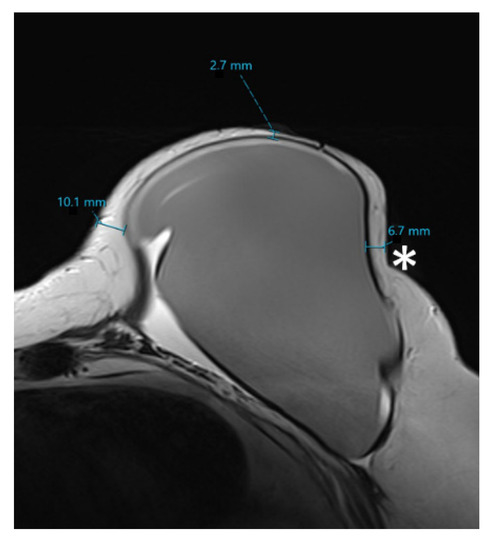

2.3. MRI Data Analysis

- Skin flap thickness at 2, 3, 4, 6, 8, 9, 10, and 12 o’clock as well as retromamillary area;

- Residual glandular tissue in retromamillary area;

- Residual glandular tissue at other location;

- Volume of the residual glandular tissue.